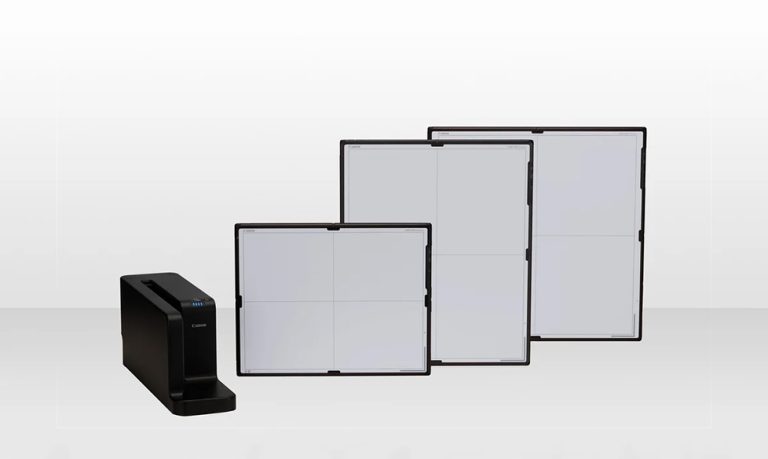

Equine Portable Digital X-Ray

Powered by the gold standard in digital radiology Canon CXDI-810C DR detector our portable equine X-Ray system is the perfect choice for equine practitioners looking for perfection.

The wireless capabilities of our Equine DR system makes it seamless to quire digital X-Ray images in the field. In just 3 seconds you are able to produce a crystal clear digital image that allows the busy practitioner to do their diagnosis right in the field reducing time to review digital images back at the office.